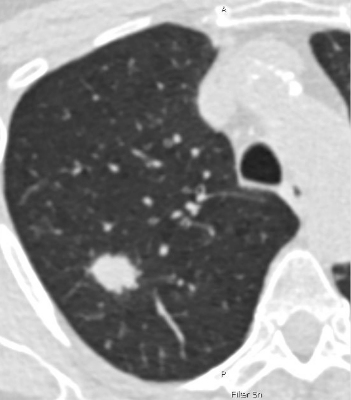

Bild: Niedrigdosis-CT-Aufnahme der Lunge einer 69-jährigen Raucherin. Die weiße rundliche Fläche im Lungengewebe deutet auf Lungenkrebs im Frühstadium hin. In diesem Stadium kann Lungenkrebs noch gut behandelt werden. © Charité | Jens Vogel-Claussen